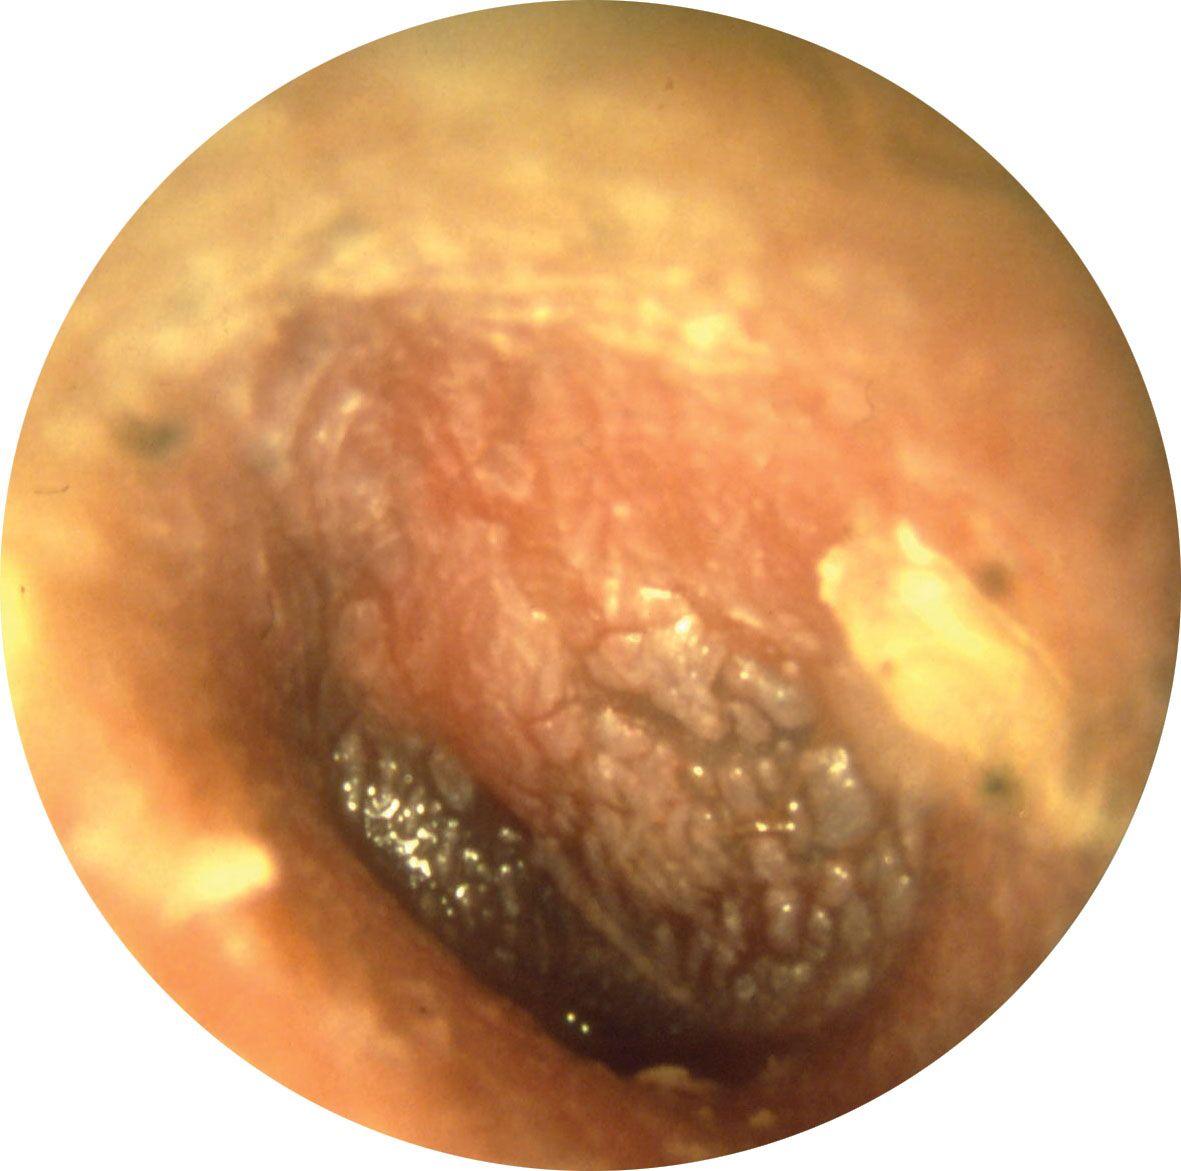

2.3 Viêm tai giữa mạn tính (giai đoạn nặng, có nguy cơ biến chứng)

Khi bệnh kéo dài mà không được điều trị đúng cách, hình ảnh viêm tai giữa ở người lớn trong giai đoạn này cho thấy tổn thương nghiêm trọng tại màng nhĩ và các cấu trúc tai giữa. Vi khuẩn có thể lan rộng, gây ra nhiều biến chứng nguy hiểm.

Dấu hiệu nhận biết qua hình ảnh

• Xuất hiện lỗ thủng trên màng nhĩ, có thể thấy dịch mủ chảy ra ngoài.

• Dịch mủ có màu vàng đậm hoặc xanh, đôi khi có mùi hôi do nhiễm khuẩn.

• Tổ chức xơ sẹo hoặc tổn thương tại khoang tai giữa, dấu hiệu của tình trạng viêm nhiễm kéo dài.

Hình ảnh viêm tai giữa ở người lớn giai đoạn mạn tính (Ảnh: Researchgate)

(*) Ghi chú:

(A) Viêm tai giữa mạn tính không hoạt động bên trái.

(B) Viêm tai giữa mạn tính hoạt động bên phải, với màng nhĩ bị viêm và niêm mạc tai giữa ẩm ướt. Hình ảnh nội soi tai sau phẫu thuật vá màng nhĩ (tympanoplasty) sau 3 tháng theo dõi

(C) Viêm tai giữa mạn tính không hoạt động dạng niêm mạc

(D) viêm tai giữa mạn tính hoạt động dạng niêm mạc

Viêm tai giữa mạn tính có mủ. (Ảnh: BMC Infectious Diseases – BioMed Central)